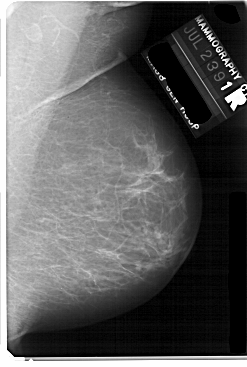

A_1738_1.RIGHT_MLO

RIGHT_MLO LINES 5491 PIXELS_PER_LINE 3691 BITS_PER_PIXEL 12 RESOLUTION 43.5 NON_OVERLAY